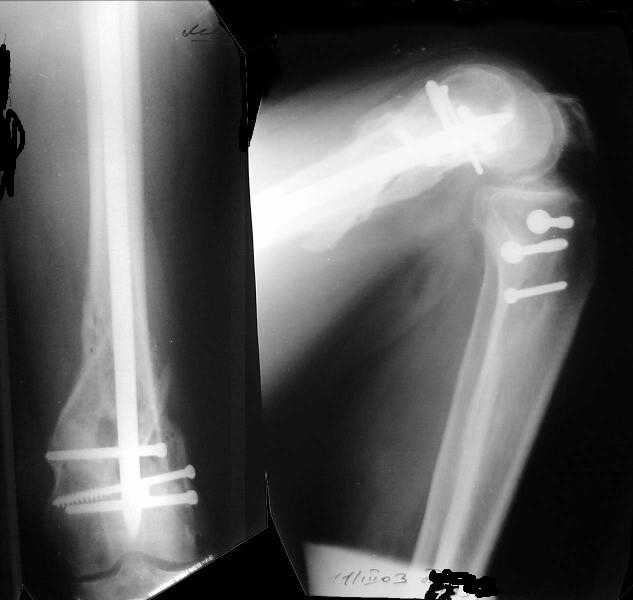

1

2

de> you think you are using antigrade nails for some very low

de> fractures including some intercondylar fractures.

Exactly. It seems the option looks underestimated.

No, i haven't seen such comparisons. However some advantages of closed antegrade nailing vs conventional plating looks self-evident like no site opeining, no bone skeletization, less blood loss, no need for autografting... If you or other colleagues can help me with the references it would be greatly appreciated. I would be interested also to compare ante- vs retrograde nailing for the localization.

de> And perhaps you could show us also some of your results ,

de> that is (follow up) not immediate postop x rays.

I attached an example of C2 fracture with result of the same technique in 5 months.